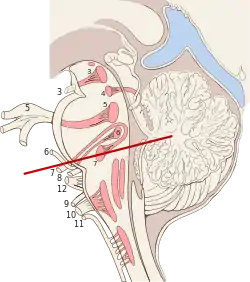

Median sagittal section of brain Nuclei of the pons and brainstem

Nuclei of the pons and brainstem Cerebrum. Deep dissection. Inferior dissection.